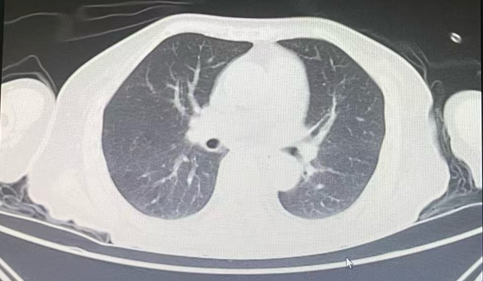

锦旗赠送人:刘女士及家人。 受表扬者:康复医学科主任衣哲、医生杨冰及其他医护人员。 近日,一面镌刻“医德高尚,仁心仁术;医术精湛,尽职尽责”的鎏金字样锦旗,被郑重送到我院康复医学科医护人员手中。这面鲜红的锦旗,承载着患者刘女士及其家属的深切感激,背后是一段跨越数月的守护历程——在医护团队协助下,曾卧床不起的刘女士逐步改善身体功能,重拾生活信心。 几个月前,一场突如其来的车祸让刘女士生命垂危。经我院ICU团队全力抢救,她的生命体征趋于稳定,但遗留颈部脊髓损伤、双下肢感觉痛觉消失等问题,需依靠气管切开套管维持呼吸、通过胃管获取营养,自主呼吸、吞咽功能丧失,生活完全无法自理。 转入康复医学科时,刘女士的状况仍面临诸多挑战。据科室衣哲主任和主管医生杨冰介绍,当时影像检查显示其肺部炎症明显、痰液淤积,日常需多次吸痰护理,部分时段需通过纤支镜清理痰液,气管切开封管与胃管拔除也需结合病情逐步推进。 针对刘女士的情况,康复医学科迅速组建由医生、康复治疗师、护士构成的协作小组。团队先对其病情进行全面评估,结合患者个体身体状况、疾病恢复阶段及家属合理期望,制定个体化、分阶段康复治疗方案,重点围绕呼吸功能改善、吞咽能力恢复、肢体活动能力提升开展工作。 康复过程中,团队先从呼吸功能干预入手:治疗师每日为刘女士进行肺部叩击、体位引流,助力气道分泌物清除;同时指导其进行缩唇呼吸训练,逐步锻炼呼吸肌力量与咳嗽能力。吞咽功能训练同步开展,治疗师采用冰刺激、空吞咽训练、门德尔松手法等方式给予指导;待其肺部炎症减轻、痰液减少后,在严密观察下尝试让她吞咽少量水与糊状食物。每一步进展,均是团队细致护理与患者积极配合的结果。 康复治疗前胸部CT提示:左肺大片状感染,左肺下叶实变,气管痰栓形成。 康复治疗后胸部CT提示:左肺感染基本吸收,原左肺实变已恢复为正常肺组织。 在呼吸、吞咽功能逐步改善的同时,肢体康复训练也有序推进。治疗师为刘女士开展关节松动术,缓解肌肉痉挛、预防关节僵硬;辅助其进行翻身训练、起立床站立训练。从需两人协助侧翻到能自主轻微移动身体,从无法坐起到顺利坐稳轮椅,过程中融入了反复的平衡训练与核心肌群强化,护士在日常护理中也会同步开展床边康复指导,鼓励刘女士主动参与,帮助其建立康复信心。 截至送锦旗当天,刘女士已在医护团队操作下成功实施气管切开套管封管、拔除胃管,能够坐在轮椅上用勺子自主进食,还能清晰向医护人员表达感谢,脸上重新展现出对生活的期待。 “这面锦旗是认可,更是我们坚守职责的动力。”康复医学科医护团队表示,科室自成立以来,始终遵循“以患者健康为中心”的服务理念,在医疗规范框架下,结合患者病情提供重症康复、功能重建、心理疏导等针对性服务,力求在专业诊疗与人文关怀上形成合力。